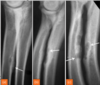

Q

identify

A

incomplete fractures